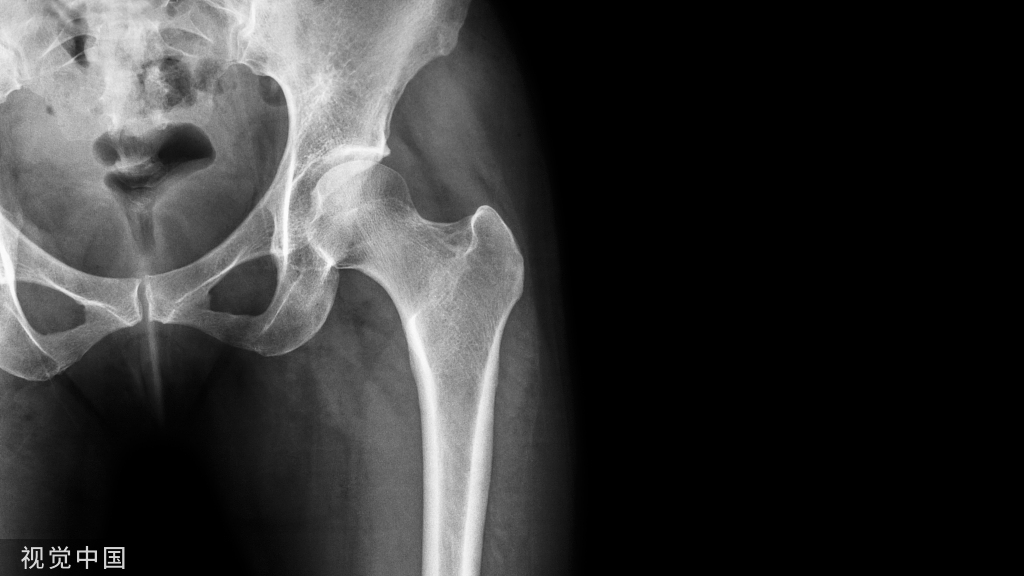

病例1:术前X线提示不稳定肱骨近端骨折,粉碎型

病例1:外侧接骨板固定,术后复查提示内翻